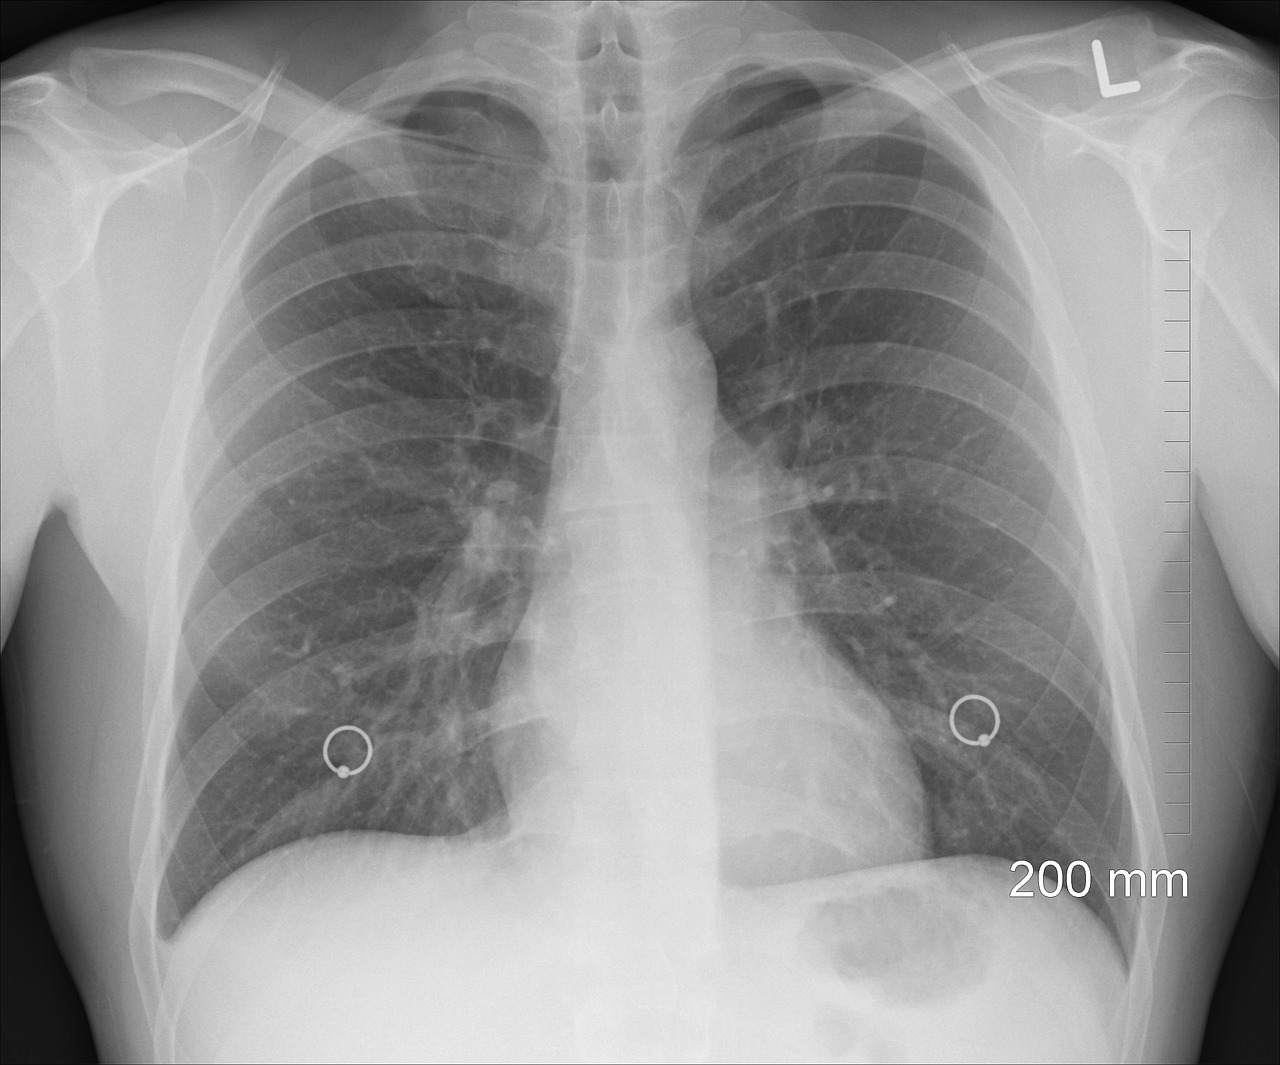

보건소에서 결핵검사를 받는 과정은 비교적 간단하며, 일반적으로 흉부 X-ray 촬영으로 진행됩니다.

- 보건소 방사선실로 이동하여 흉부 X-ray 촬영을 진행합니다.

보건소 결핵검사는 저렴한 비용(2,000원~3,000원)으로 받을 수 있으며, 흉부 X-ray 검사로 간단하게 진행됩니다.